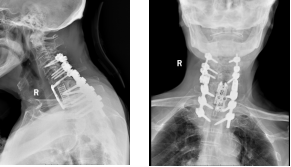

面对如此复杂且高风险的病情,我院骨科团队高度重视,迅速联合多学科周密评估,为患者实施了前后联合入路颈椎骨折切开复位内固定+椎管减压+椎体次全切+钛网及钢板内固定术。这一手术技术难度较高,对医护团队的专业水平和协作能力都是巨大的考验。在充分的术前准备后,手术如期进行。骨科团队凭借精湛的技术和丰富的经验,沉着冷静地应对每一个环节,经过紧张奋战,手术顺利完成。

术后,患者颈部剧烈疼痛及右肩右上肢放射疼痛立即减轻,一周后,颈部疼痛及右上肢放射痛消失,脊柱形态得到显著改善,已能重新直立站立行走。

从术前的佝偻体态,到术后重新挺直颈部和腰板,生活质量明显提高。老人的康复变化,直观体现了手术与护理的显著成效,也彰显了我院骨科在高龄复杂脊柱创伤救治领域的过硬实力。